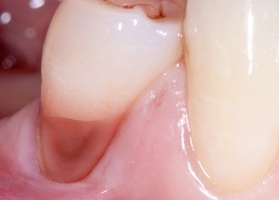

Gum plastics in the area of FDM with autograft No. 1

14 september 2018